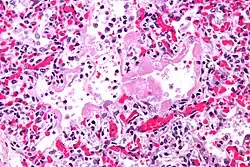

| Micrograph showing hyaline membranes, the key histologic feature of diffuse alveolar damage. H&E stain. | |

- Diffuse alveolar damage (DAD): an acute lung condition with the presence of hyaline membranes.[2] These hyaline membranes are made up of dead cells, surfactant, and proteins.[1] The hyaline membranes deposit along the walls of the alveoli, where gas exchange typically occurs, thereby making gas exchange difficult.

- The edema contributes to the deposition of a hyaline membrane (composed of dead cells, surfactant, and proteins) along the alveolar walls. Hyaline membranes are characteristic of DAD.

In order to make a diagnosis of DAD a biopsy of the lung must be obtained, processed, and examined microscopically. As described above, the hallmark of diagnosing DAD is the presence of hyaline membranes.[1] Most frequently DAD is associated with ARDS, but since there are clinical criteria (see Berlin criteria above) upon which we can diagnose ARDS, it is often unnecessary in all cases to obtain invasive biopsies of the lung. Additionally, there are limitations of the biopsy test since it is possible to sample a potentially normal area of lung even though there is DAD in the rest of the lung, resulting in a false negative.[1]